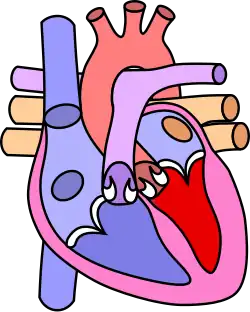

![]() | |

| Diagram of a healthy heart and one with the tetralogy of Fallot | |